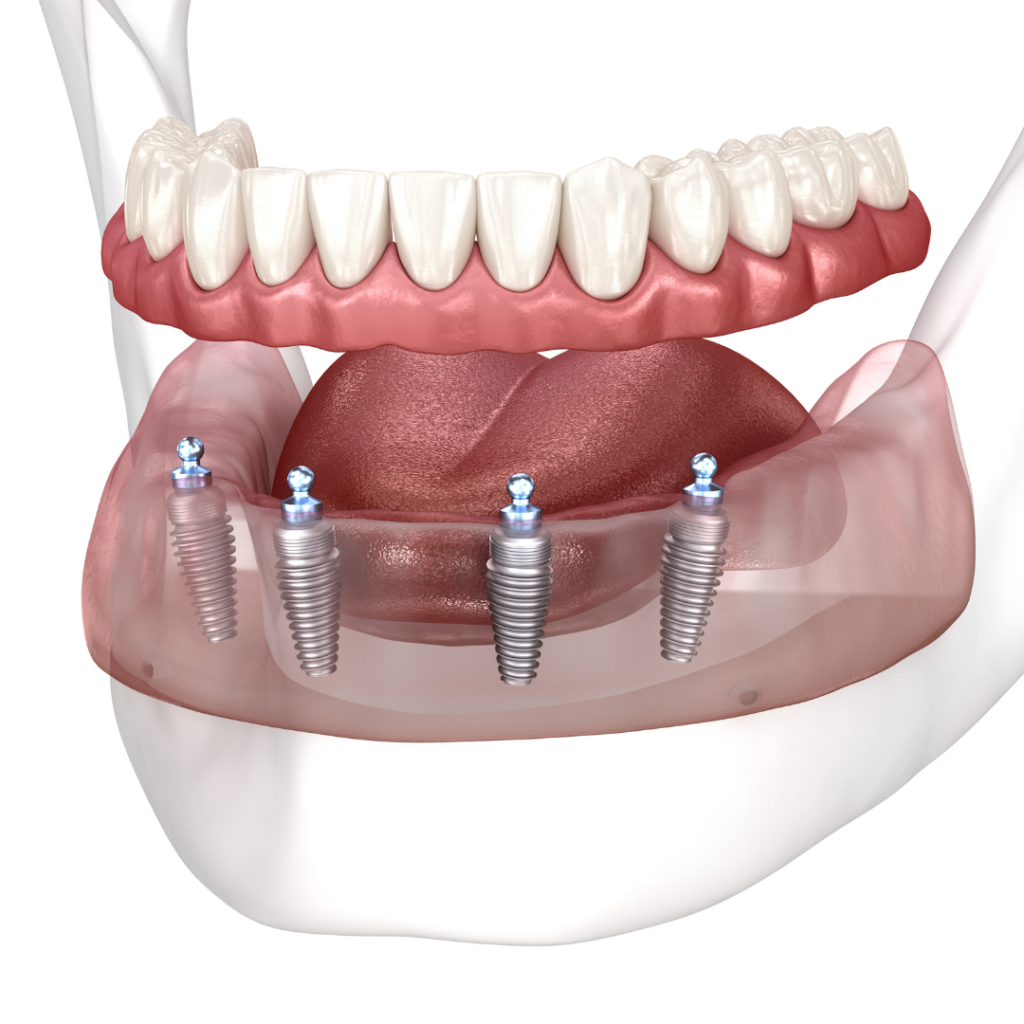

Every single dental implant consists of three parts – the implant, the abutment, & the crown. The implant is made of medical grade titanium. This part is surgically placed into the patient’s jaw bone and left to heal for 4-6 months afterwards.

This implant piece acts as the foundation for the rest of the tooth. Once the bone around the site has healed, the abutment and crown are placed on top of the implant. The end result is a beautiful, natural-looking new tooth!

Few people will ever be able to tell the difference between your implants and your real teeth.